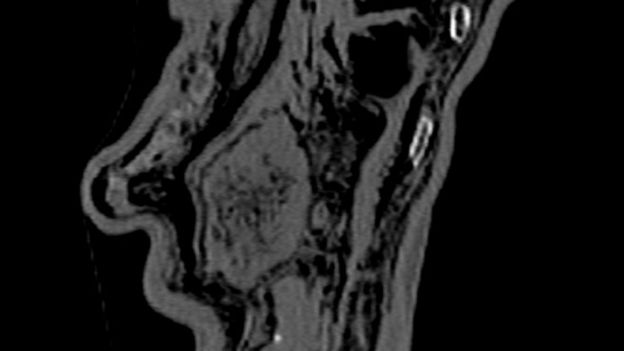

X-ray imaging of the Iceman’s stomach and intestineImage copyrightCentral Hospital Bolzano

Image captionThe microbes were extracted from Oetzi's intestines and stomach wall, shown here in an x-ray